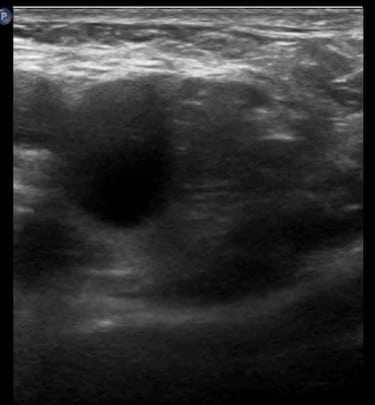

Ultrassonografia na avaliação de hérnias femorais

A USG é amplamente utilizada na avaliação de hérnias devido à sua acessibilidade, baixo custo e ausência de radiação ionizante. Ela permite a visualização dinâmica das estruturas abdominais em tempo real, facilitando a identificação de hérnias e suas complicações. Contudo, a precisão do exame depende da técnica empregada e da experiência do operador.

Técnica de USG na identificação de hérnias femorais

Deve-se utilizar um transdutor linear com auxílio do gel. Deve-se identificar o ligamento inguinal com o aparelho, onde será possível visualizar os vasos inguinais, veias e artérias femorais.

As hérnias femorais apresentam-se em uma topografia específica, na região exata, medial à veia femoral. A partir da inserção do transdutor na inserção ideal para avaliar este tipo de hérnia, podemos pedir ao paciente para realizar a manobra de Valsalva.